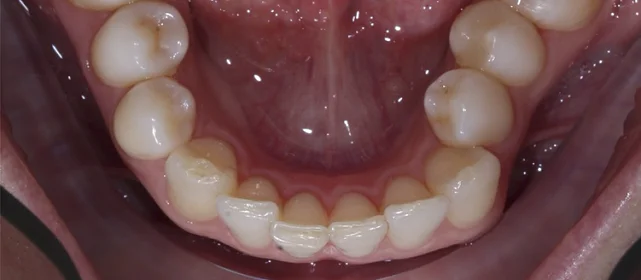

Обе челюсти сужены — зубам не хватало места, они стояли скученно на верхней и нижней челюсти. Нарушена кривая смыкания — жевательные зубы были на разной высоте.

Проблема: Пациентка живёт за рубежом и обратилась с жалобами на неровные зубы. При осмотре обнаружили сужение обеих челюстей, скученность на верхней и нижней, а также деформацию кривой смыкания — жевательные зубы стояли на разной высоте, из-за чего нагрузка при еде распределялась неравномерно. Дополнительная сложность — пациентка не могла приезжать на визиты часто.